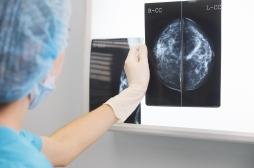

tumeur

LES MALADIES